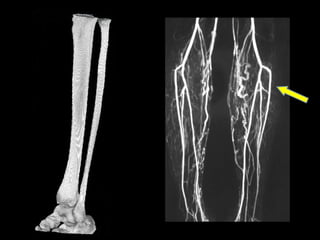

Evitar contaminación de campos. Mayor eficiencia al planificar y realizar las osteotomías mandibulares. Mayor eficiencia al planificar y realizar las osteotomías del peroné.

Evitar contaminación decampos. Mayor eficiencia al planificar y realizar las osteotomías mandibulares. Mayor eficiencia al planificar y realizar las osteotomías del peroné.